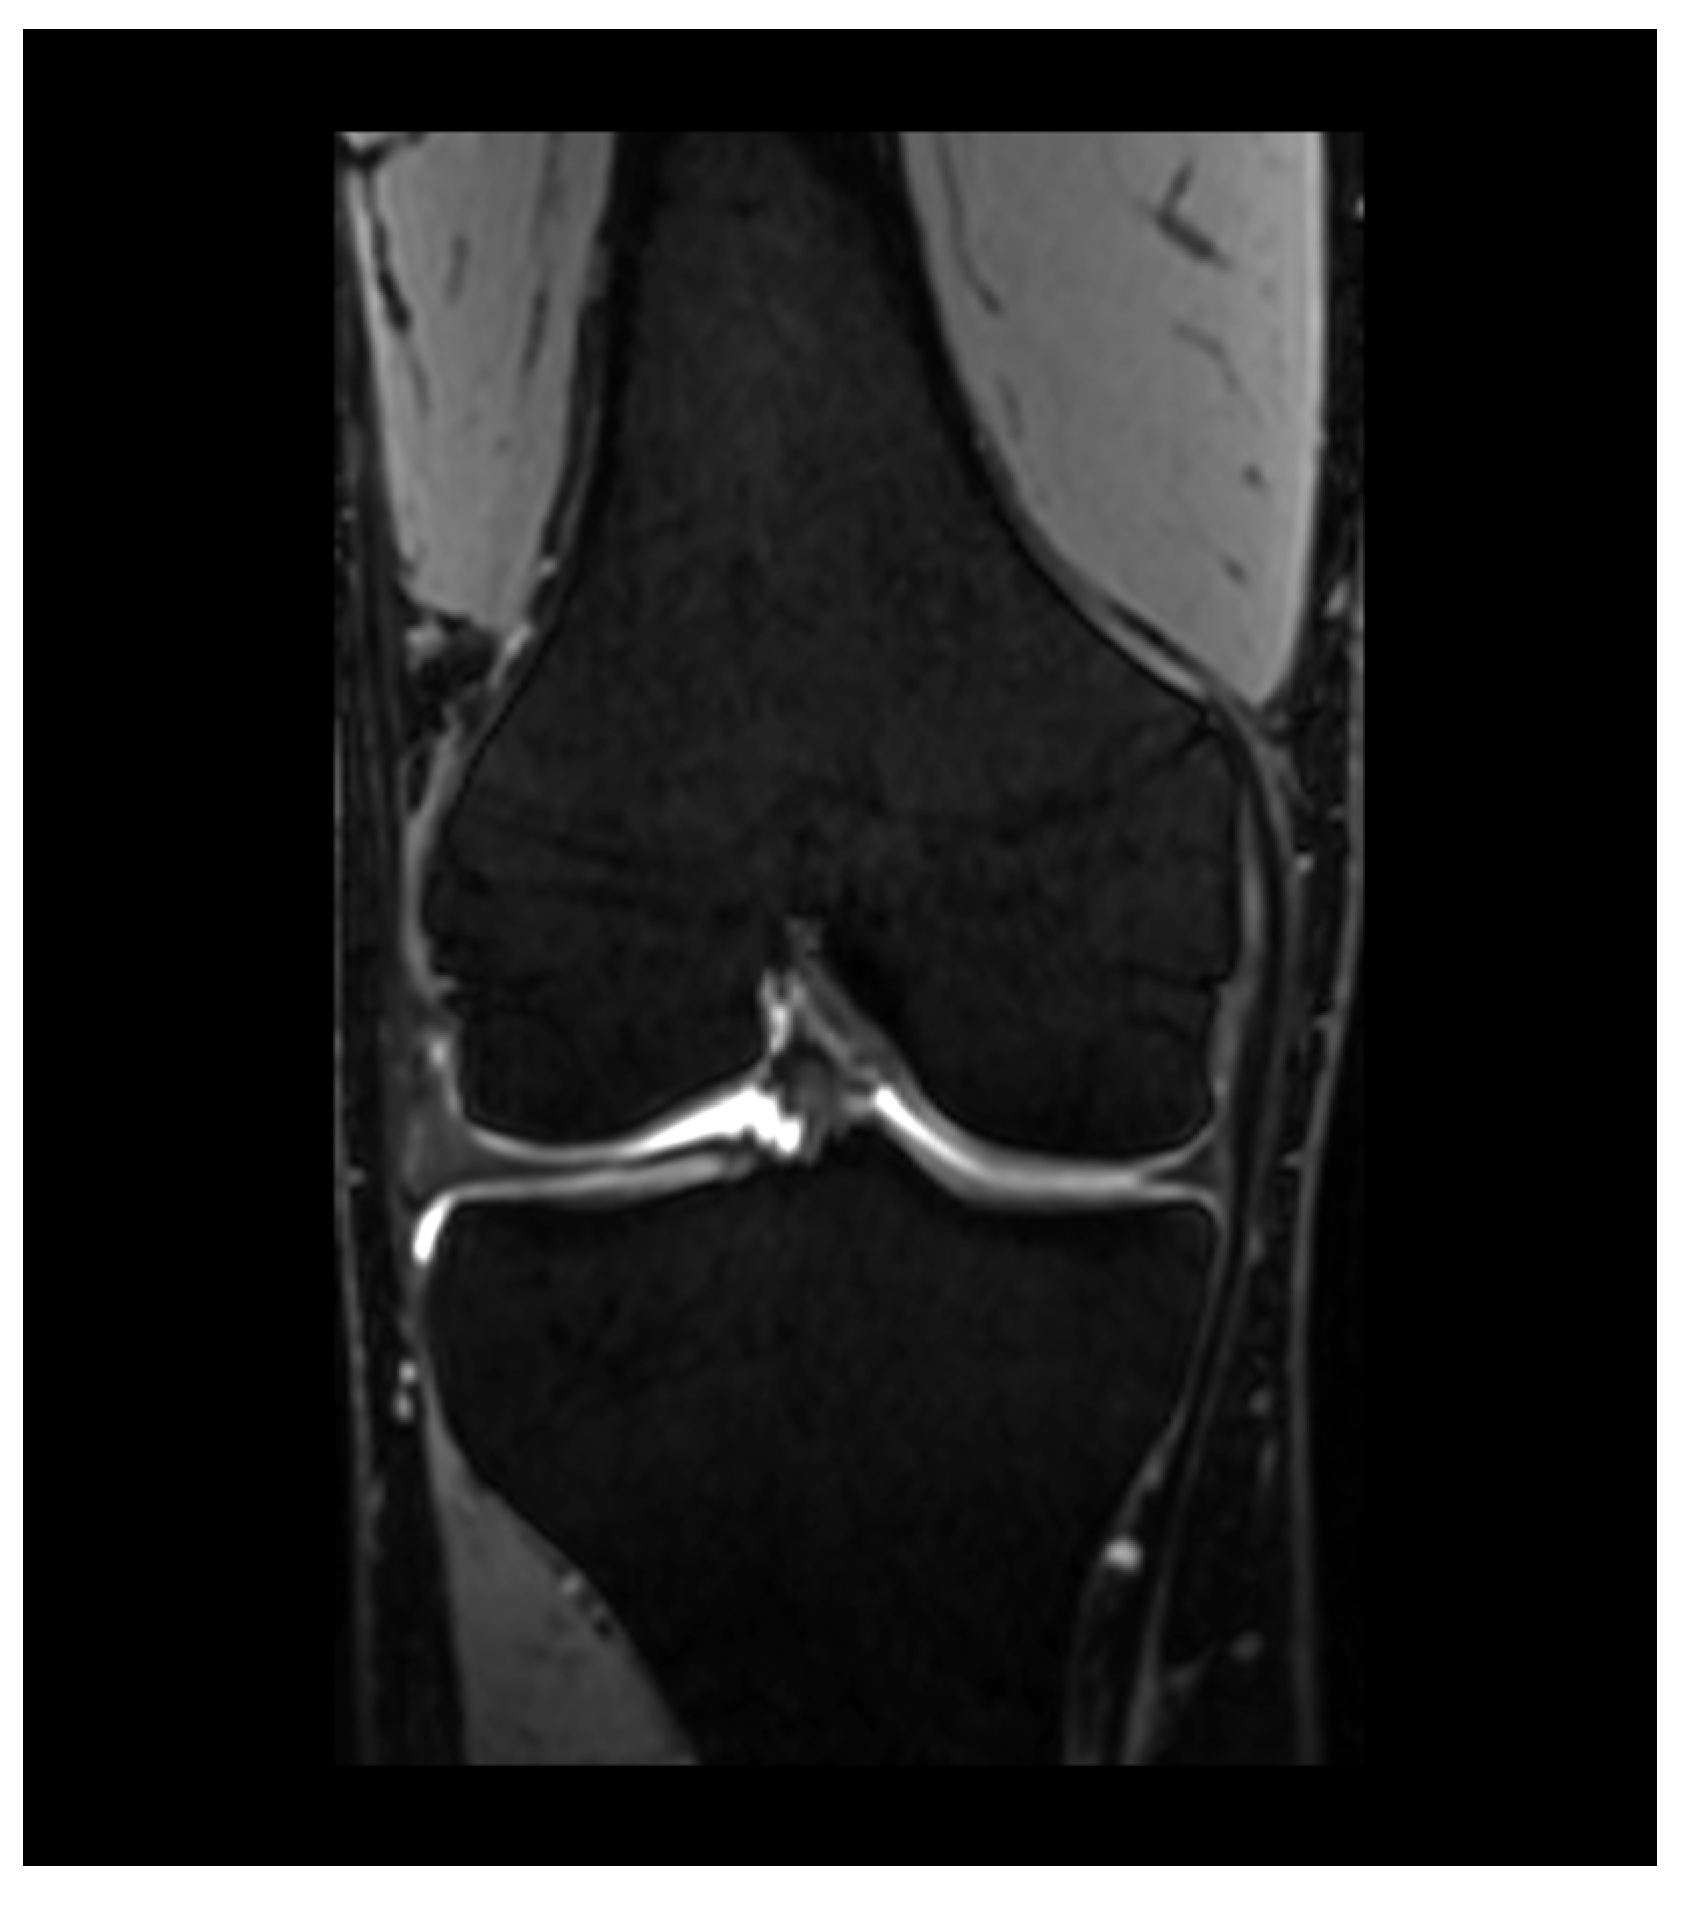

6.3. T2 Mapping

- Dunn, T.C.; Lu, Y.; Jin, H.; Ries, M.D.; Majumdar, S.; Roemer, F.W.; Demehri, S.; Omoumi, P.; Link, T.M.; Kijowski, R.; et al. T2 Relaxation Time of Cartilage at MR Imaging: Comparison with Severity of Knee Osteoarthritis. Radiology 2004, 232, 592–598. [Google Scholar] [CrossRef]

- Koff, M.; Amrami, K.; Kaufman, K. Clinical evaluation of T2 values of patellar cartilage in patients with osteoarthritis. Osteoarthr. Cartil. 2007, 15, 198–204. [Google Scholar] [CrossRef]